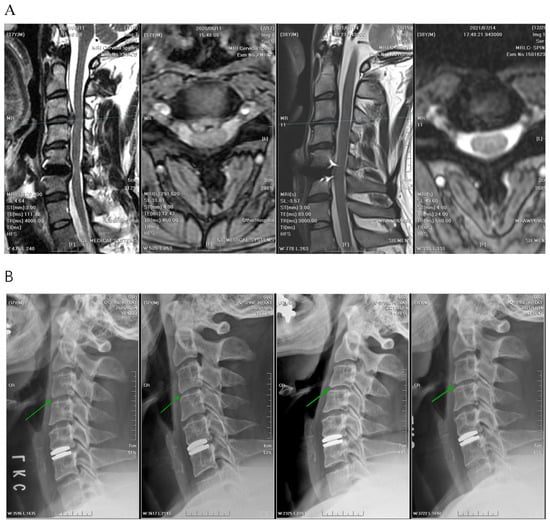

2. Materials and Methods

2.1. Patient Information

2.2. Patient Selection

2.3. Clinical and Radiological Parameters

2.4. Preoperative Workup, Positioning, and Operative Technique

2.5. APECD

2.6. PPECD

3.4. Radiographic Outcomes